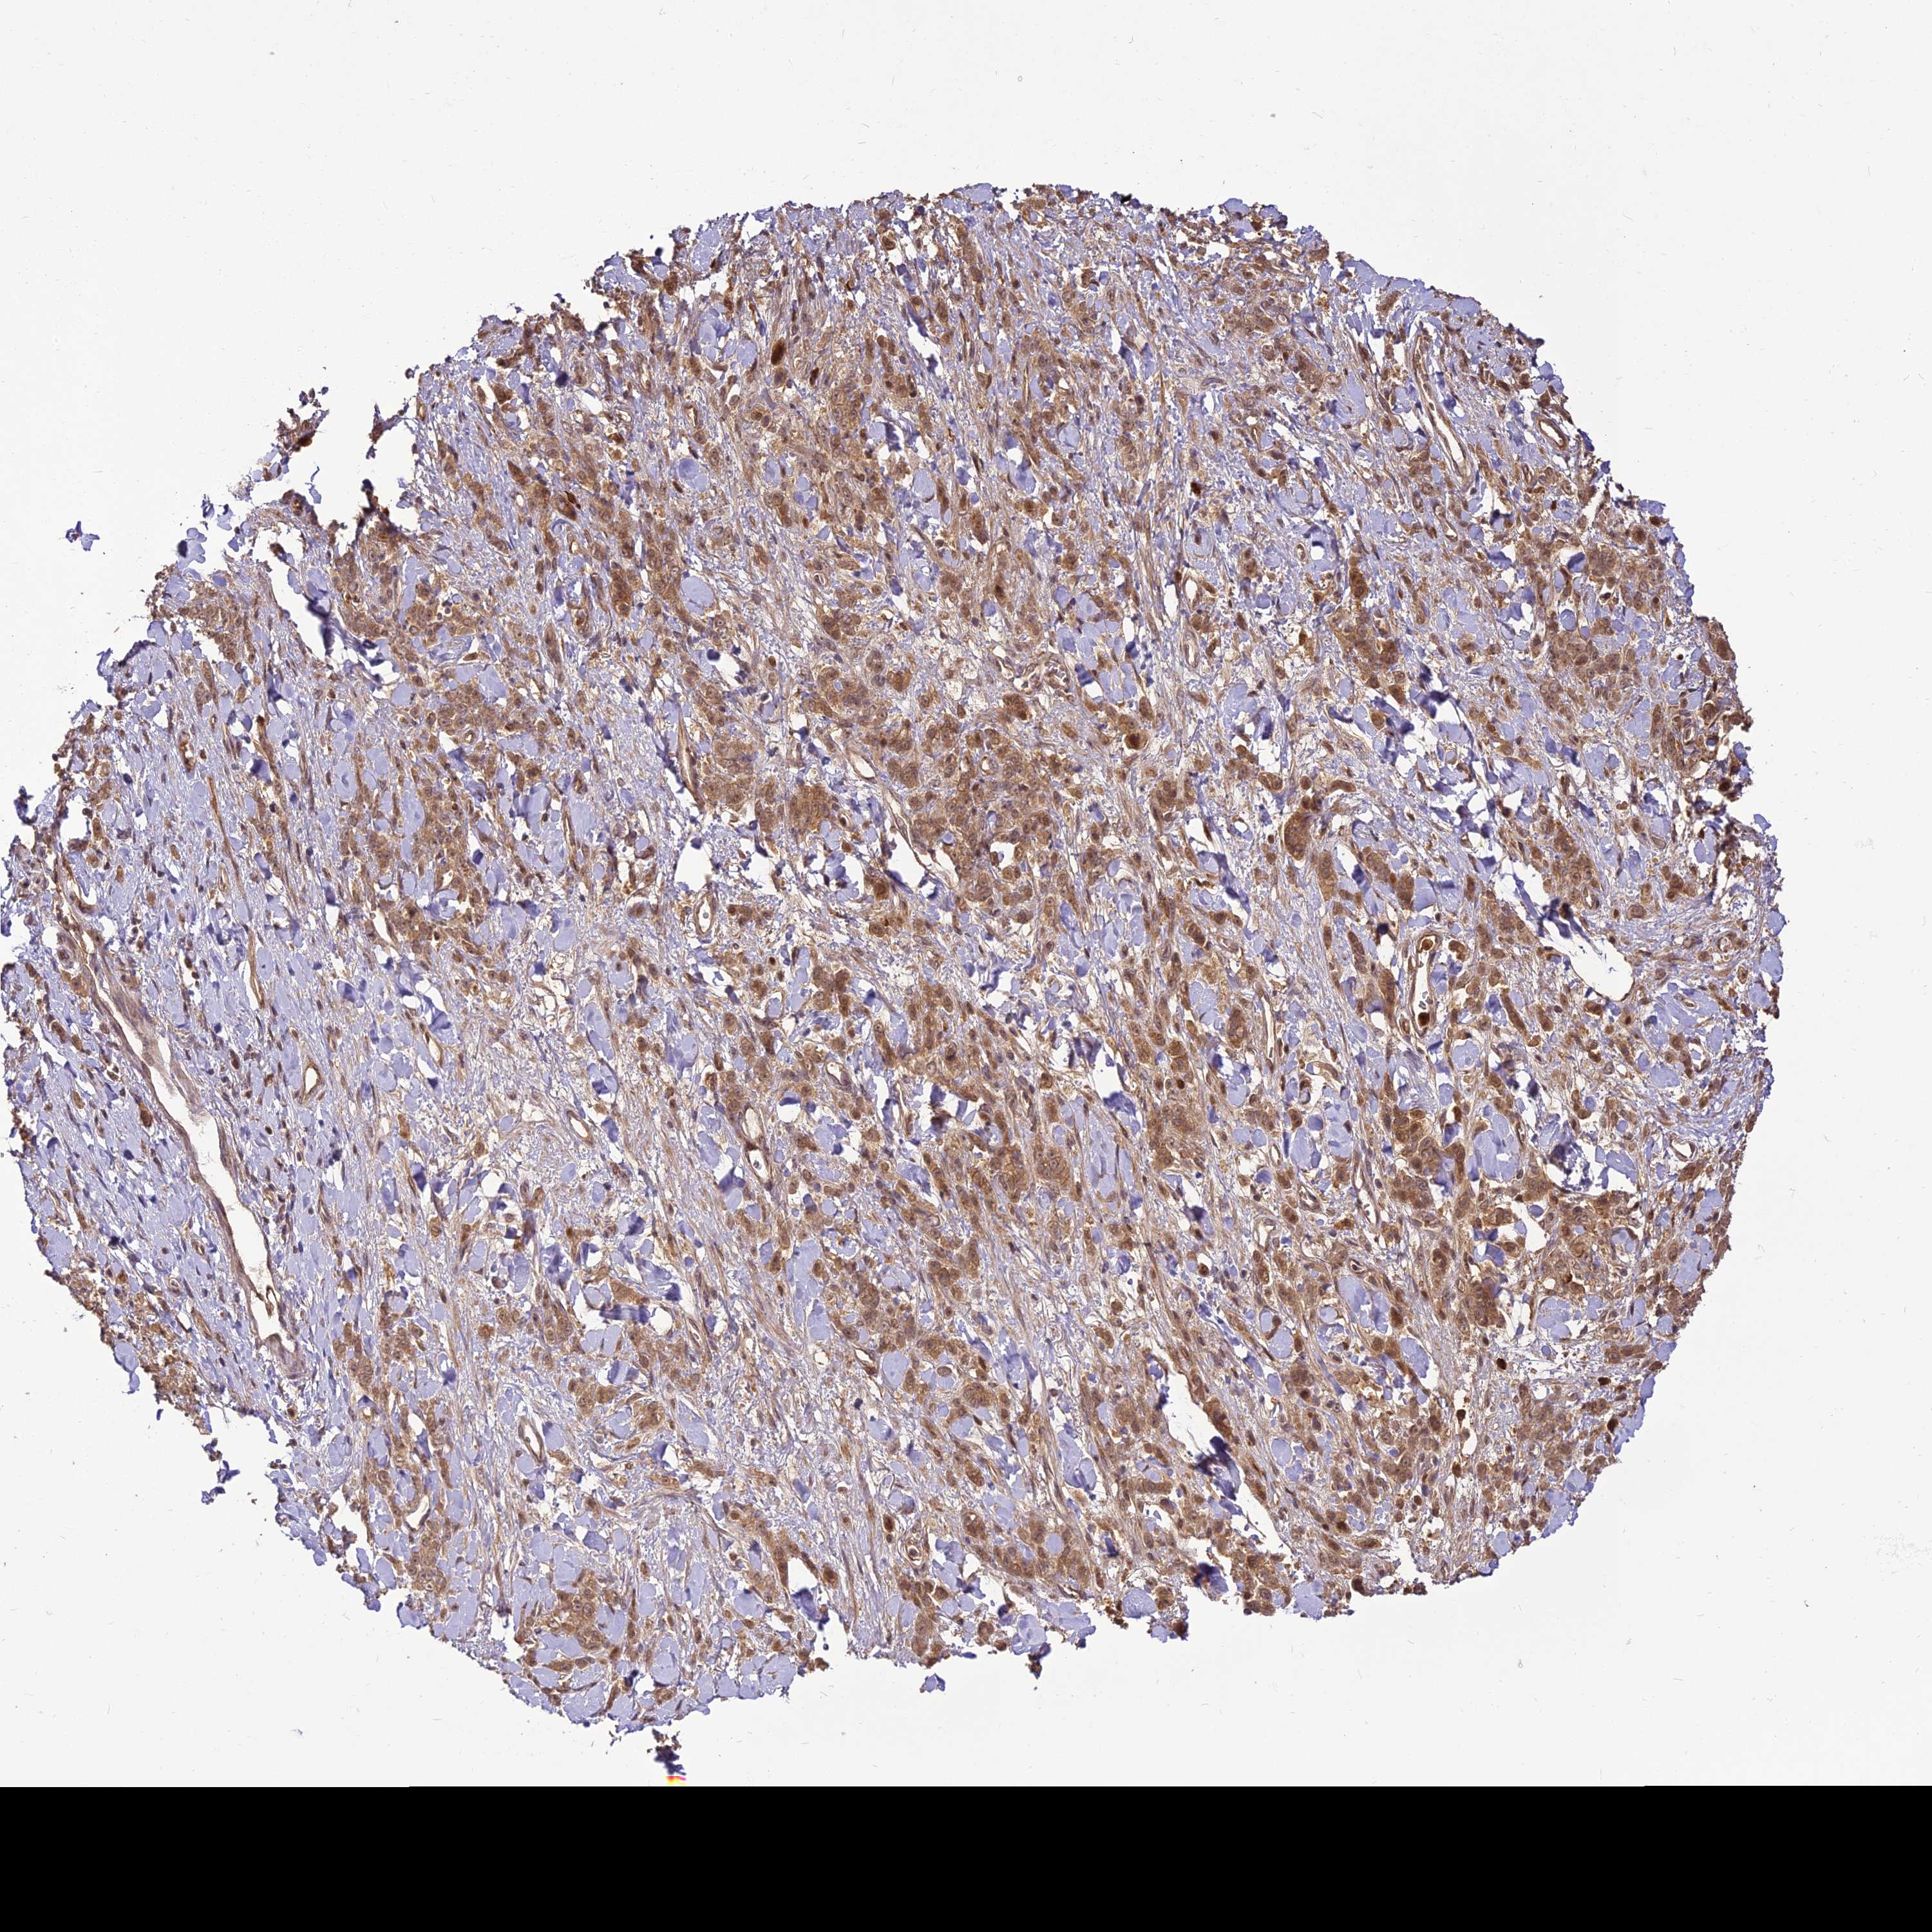

STOMACH CANCER - Protein expressioni

A mouse-over function shows sample information and annotation data. Click on an image to view it in a full screen mode. Samples can be filtered based on level of antibody staining by selecting one or several of the following categories: high, medium, low and not detected. The assay and annotation is described here.

Note that samples used for immunohistochemistry by the Human Protein Atlas do not correspond to samples in the TCGA dataset.

Antibody stainingi

Antibody staining in the annotated cell types in the current human tissue is reported as not detected, low, medium, or high, based on conventional immunohistochemistry profiling in selected tissues. This score is based on the combination of the staining intensity and fraction of stained cells.

Each image is clickable and will lead to virtual microscopy that enables deeper exploration of all samples and also displays staining intensity scores, fraction scores and subcellular localization as well as patient and tissue information for each sample.

Antibody HPA039911

Staining

High

Medium

Low

Not detected

Intensity

Strong

Moderate

Weak

Negative

Quantity

>75%

75%-25%

<25%

None

Location

Nuclear

Cytoplasmic/membranous

Cytoplasmic/membranous,nuclear

Adenocarcinoma, NOS